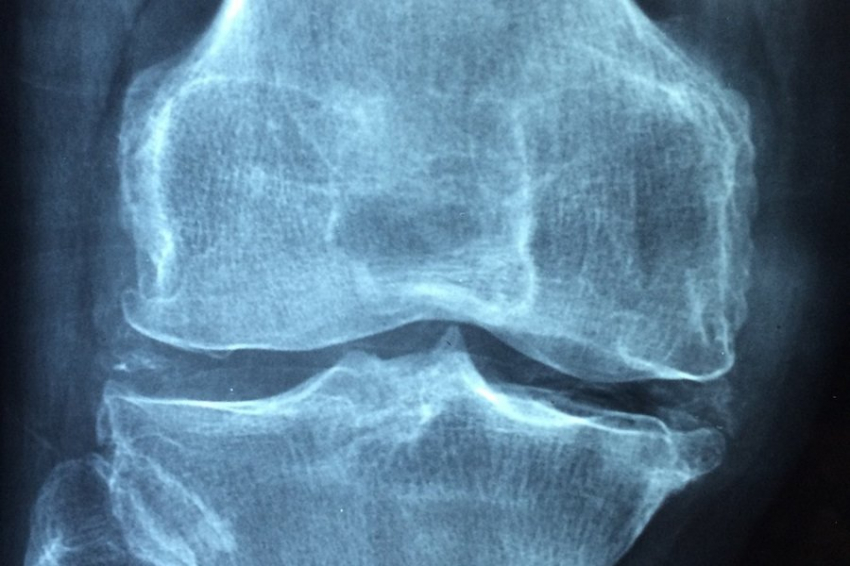

Nature Nanotechnology: представлен метод лечения артрита с помощью наночастиц

Учеными из Сеульского национального университета Республики Корея представлена новая методика лечения ревматоидного артрита при помощи наночастиц.